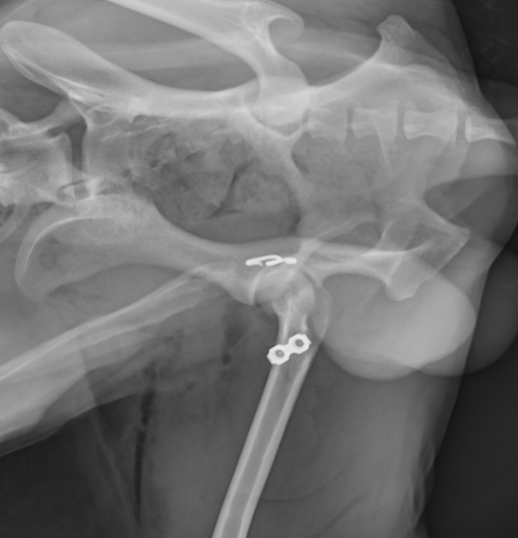

まずはワッシャーによる固定をご紹介します。大腿骨の大転子という部分を一時的に切断してから、骨盤臼にアプローチしてワッシャーを1つか2つ打ち込み、そこと大腿骨頭の骨頚部と呼ばれる部分に穴を開けてワイヤーを通し骨盤と大腿骨を固定する方法です。2週間ほど脱臼せずに維持できればその後は安定化していきます。